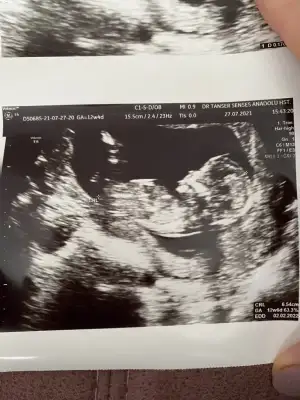

Doktor simdilik kiz diyelim dedi ama bakalm sabaha randevumuz var gozukurse yazicam insallah saglikla gelsin de hic farketmez sagolasin cevabin icin bide son ultrasonu atayim ona da bakiverErkek gibi

Doktor simdilik kiz diyelim dedi ama bakalm sabaha randevumuz var gozukurse yazicam insallah saglikla gelsin de hic farketmez sagolasin cevabin icin bide son ultrasonu atayim ona da bakiver![]()

Evet burada bacak arası boş görünüyor sağlıkla gelsin prenses